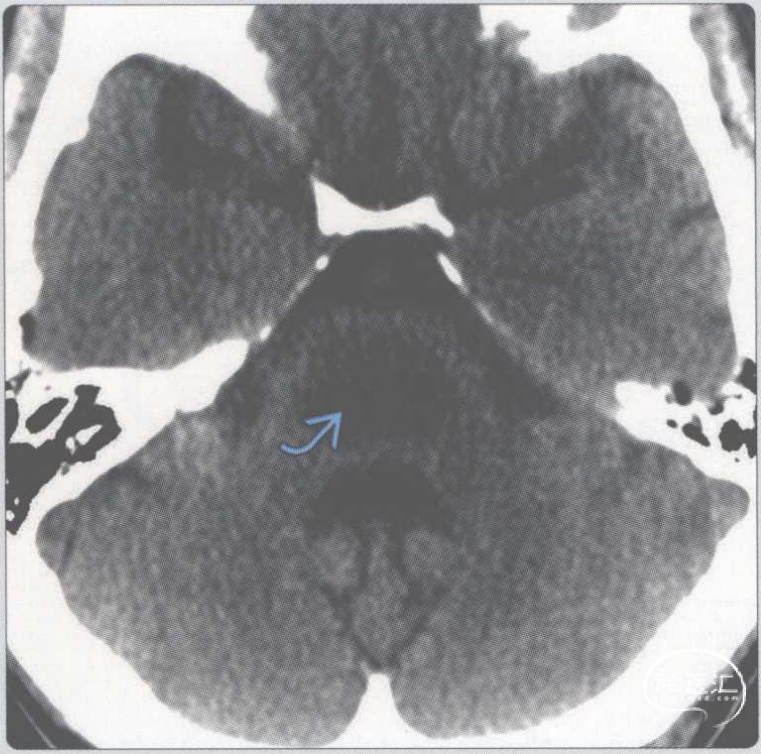

【影像时间·236】一例表现为感觉异常的长期酗酒患者